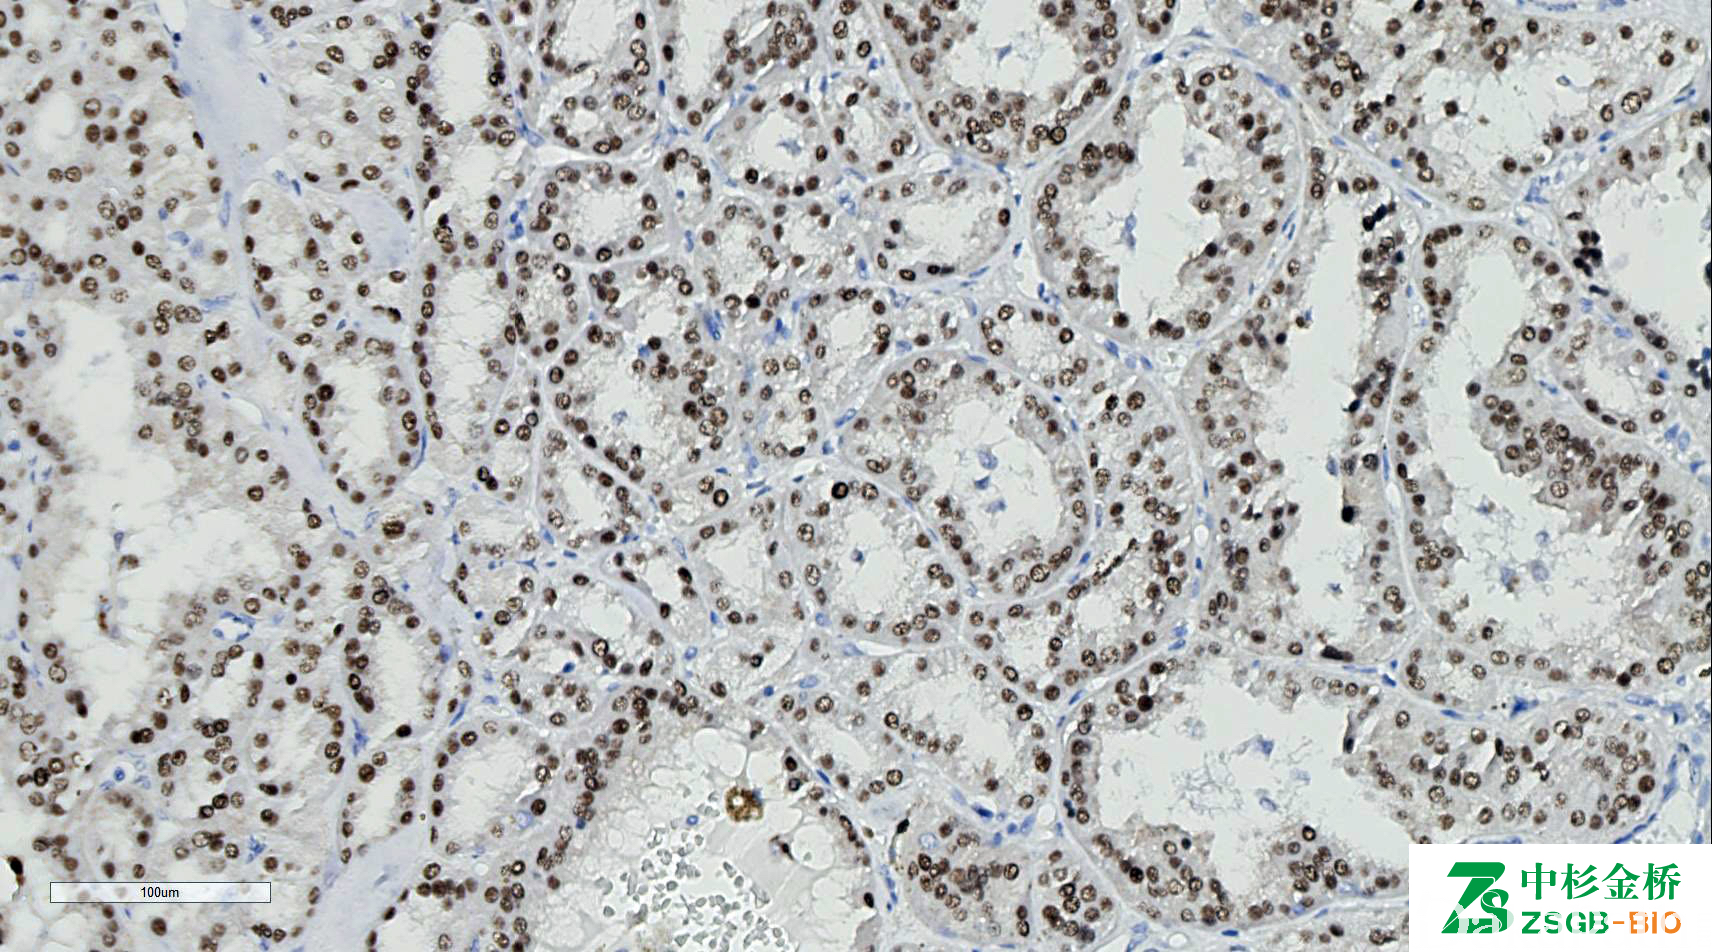

TFE3 基因定位于 X 染色体短臂,在正常细胞均有弱的表达,在 Xp11.2 易位/TFE3 基因融合相关性肾细胞癌和 ASPL/TFE3 基因融合腺泡状软组织肉瘤中弥漫强阳性。

信号定位: 胞核

几乎全部阳性(≥95%的病例阳性): 肾细胞癌伴 Xp11.2 异位、腺泡状软组织肉瘤